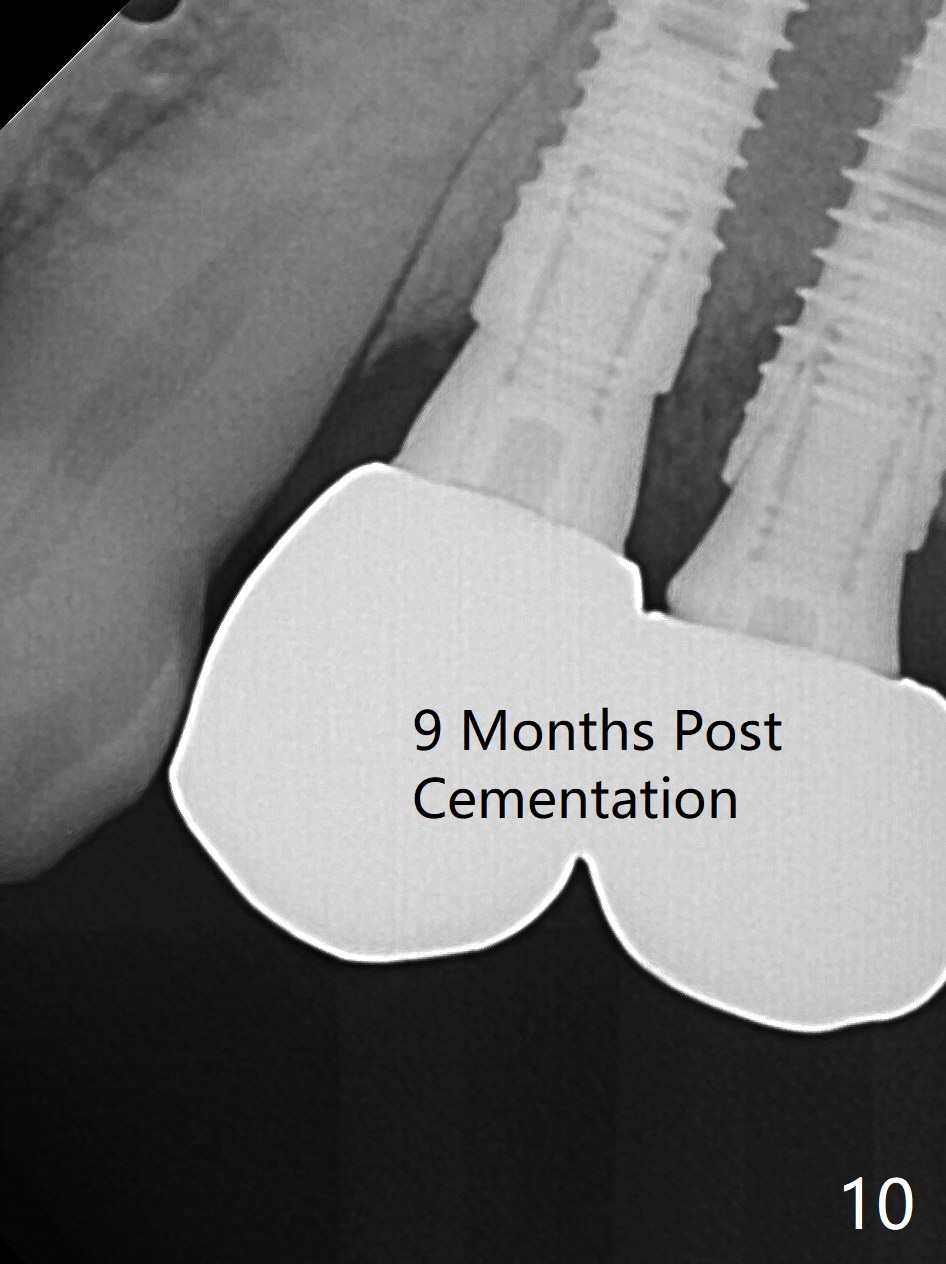

The buccal gingiva at #12 with vertical root fracture looks unhealthy (Fig.1). Osteotomy at #13 is initiated prior to #12 extraction. In fact the osteotomy happens in the extensive defect associated with #12 (Fig.2 red dashed line). To obtain primary stability, the osteotomy at #12 needs to be long, while that at #13 needs two-pointed fixation (Fig.3 *). After adjustment of trajectory at #12 and increase in diameter of the osteotomy at #13 (Fig.4), a 3.8x15 and 3.8x10 mm implants are placed (Fig.5). Following adjustment of implant depth (Fig.6), the implant at #12 becomes loose, while that at #13 tightens. With placement of abutments, an immediate splinted provisional is locked in place to stabilize the loose implant at #12 (Fig.7). The patient complains of cold sensitivity in the upper left quadrant, possibly related to the fact that the implant at #12 is close to the apex of the tooth #11. The position and trajectory of the initial osteotomies should be changed as shown in Fig.8 (white lines, as compared to Fig.2). There is no sensitivity 1 month postop. Impression is taken 4 months postop (Fig.9) after #13 mesiobuccal margin prep. The implants were placed too close to each other. The abutment screw at #13 is retightened 8 months post cementation. There appears no bone loss 9 months post cementation (Fig.10), while the tooth #11 has periapical infection with DL caries 1 year 7 months post cementation (Fig.11).